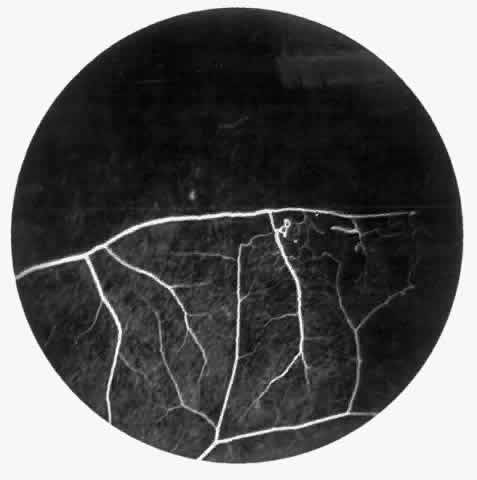

STAGE I: PERIPHERAL ARTERIOLAR OCCLUSIONS. This stage may be further subdivided into three grades: grade I, narrowing of the peripheral arterioles with tortuosity and abnormal looping of the peripheral venules; grade II, tortuosity, dilation, and microaneurysmal formation in the capillary network; and grade III, occlusion of the peripheral capillaries and arterioles.83

Histologic and trypsin digest studies support the theory of a sudden occlusion of the precapillary arteriolar circulation followed by degeneration of the occluded vessels and the distal nonperfused retina. The presence of focal areas of small vessel degeneration and vascular beading (but not typical retinal microaneurysms) also have been confirmed.132

The occluded arterioles may be invisible or may have a “silver-wire” or chalk-white appearance, as first described by Goodman and colleagues39 (Fig. 21). Fluorescein angiography may demonstrate an abrupt complete occlusion at the interface between peripheral nonperfused and posterior perfused retina. Frequently, this occlusion will take place just distal to a branching vessel, giving the appearance of a freshly pruned rose bush. The nonperfused anterior peripheral retina will have a grayish brown appearance and on fluorescein angiography will appear blurred without clearly defined fundus markings.

Fig. 21. A. Photograph of the peripheral retinal vasculature shows sheathed vessels and absence of peripheral vascular perfusion. B. Fluorescein angiogram shows area of nonperfusion representing stage I sickle cell retinopathy. White arrow points to corresponding vascular bifurcation in A and B.